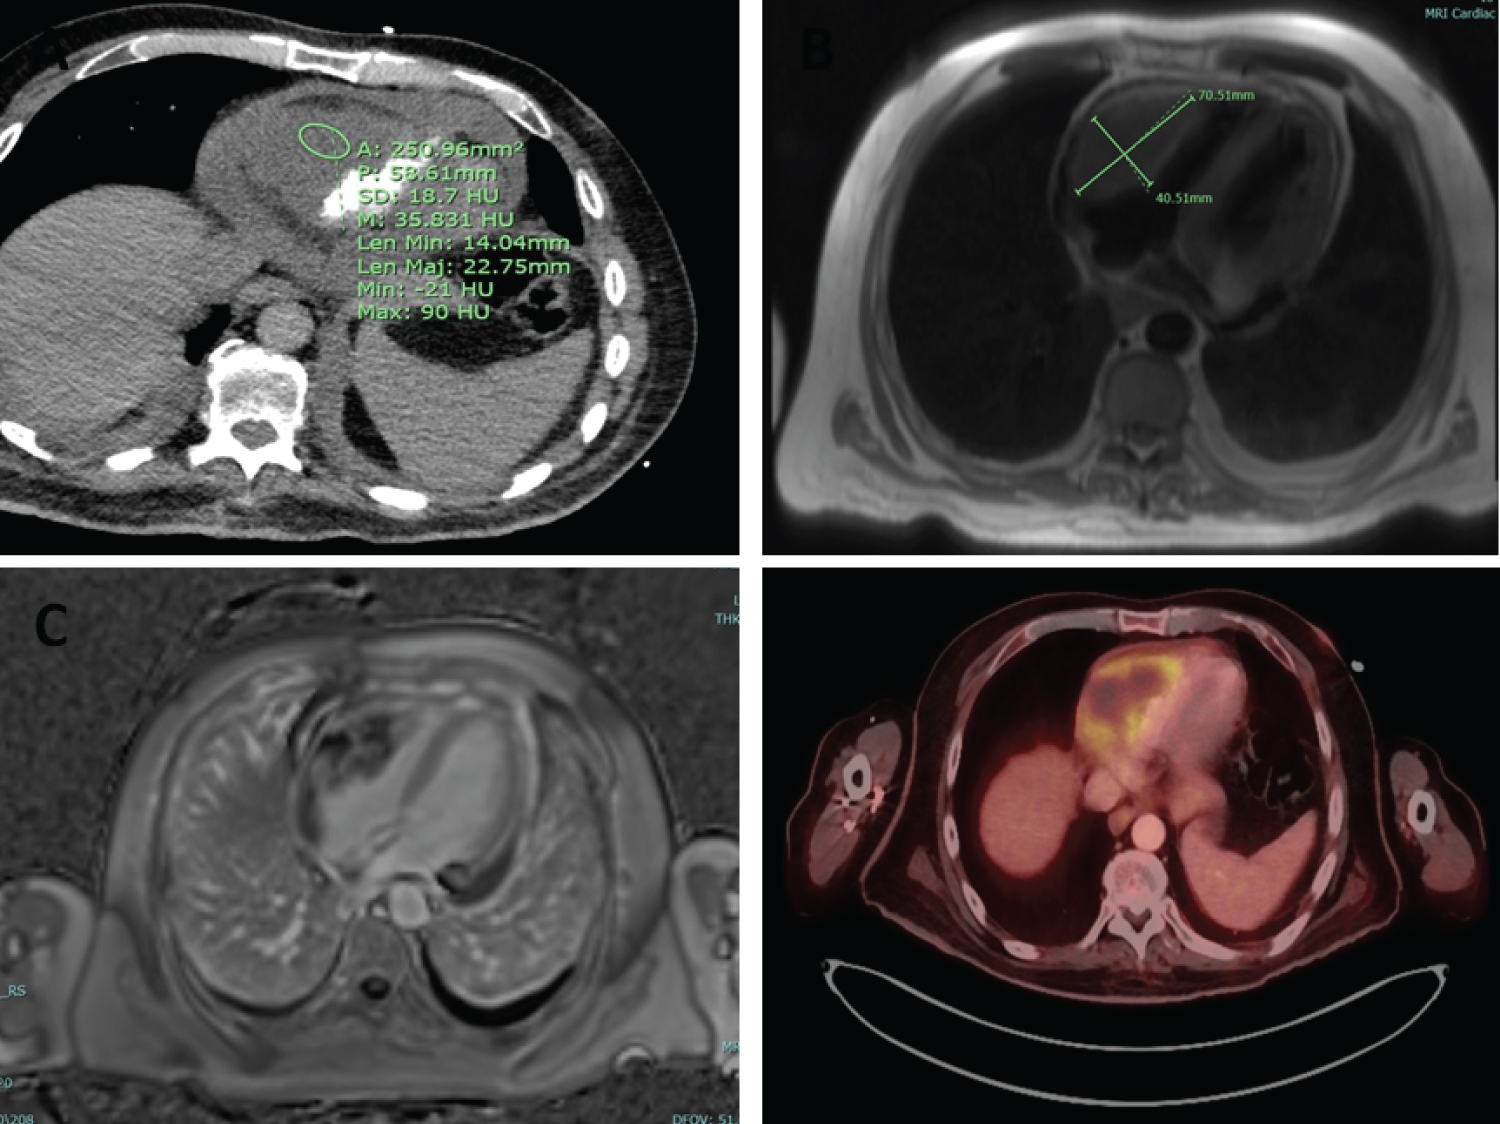

Figure 1: A) CT scan showing moderate to large pericardial effusion and a lobular hypodense mass along the visceral pericardium/ epicardium of right heart border; B) T2 weighted cardiac MRI image showing a ~7.1 × 4.1 cm mass arising from the wall of the RV and extending into the RV outflow tract; C) MRI image of RV mass showing delayed enhancement; D) PET Scan showing 8.7 × 4.7 × 6.8 cm hypermetabolic mass involving the right ventricle with mass effect on the ventricular ligament. View Figure 1

A 57-year-old male with a history of oropharyngeal squamous cell carcinoma treated with radiation and seven rounds of cetuximab, subsequently in remission, presented with dyspnea along with face and neck swelling. On physical exam, vital signs were within normal limits. Head and neck exam notable for swelling and firmness bilaterally and right L2 lymphadenopathy. Cardiopulmonary exam was unremarkable. Complete blood count showed normal cell line counts and metabolic panel was at baseline. CT head and neck showed large mass at base of tongue consistent with reoccurrence of malignancy. CT Imaging also revealed a moderate-to-large pericardial effusion and a mass along the epicardium (Figure 1A). Echocardiogram showed a large pericardial effusion and a right ventricular (RV) mass (Figure 2). For further characterization of current presentation, patient underwent a Lymph node biopsy which was consistent with PDL-1 positive metastatic HNSCC.

A pericardiocentesis was attempted for pericardial fluid analysis, however, was unsuccessful due to small fluid accumulation. Subsequent echocardiogram showed resolution of the pericardial effusion. A Cardiac MRI confirmed the presence of a vascular RV mass with peripheral delayed enhancement (Figure 1B and Figure 1C). An endomyocardial biopsy using standard myocardial bioptome via transfemoral approach was attempted but yielded benign fibrinous endomyocardial tissue likely due to the epicardial location of the tumor. The cardiothoracic surgery team evaluated images and relayed that to obtain a meaningful tissue sample, the patient would have to be put on cardiopulmonary bypass, a high-risk procedure in the setting of his already advanced cancer. Chemotherapy options depended on whether the cardiac mass was primary versus secondary malignancy. Another endomyocardial biopsy was pursued, this time using ICE guidance, again yielding benign tissue. The Oncology team communicated that if the pathology was yielding benign tissue, they had to suspect the patient may have a new primary angiosarcoma and would not qualify for further chemotherapy.